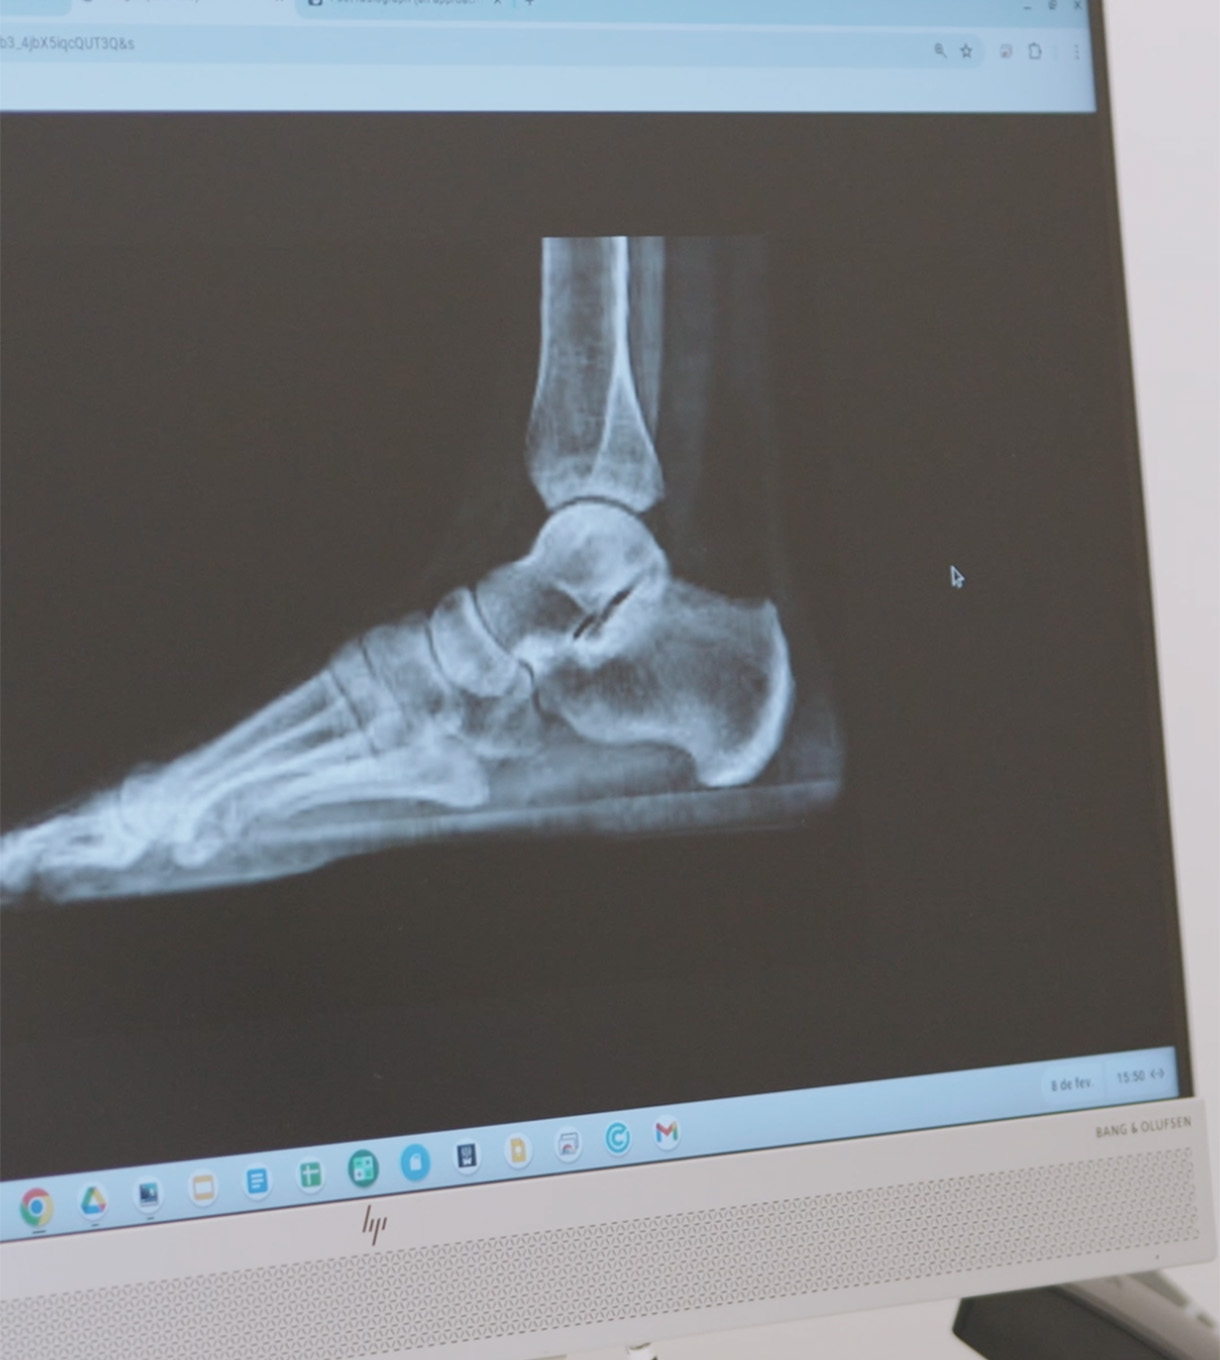

A Unidade do Pé e Tornozelo do grupo ORTOCENTRO, a funcionar no Hospital CUF Trindade, é dirigida por especialistas altamente diferenciados no diagnóstico e tratamento das lesões do pé e tornozelo.

Os pacientes que visitam esta unidade beneficiam de uma abordagem multidisciplinar com reumatologistas, médicos especialistas em medicina desportiva, ortopedistas, enfermeiros especializados, fisioterapeutas, terapeutas ocupacionais e podologistas .

Trauma - fracturas do tornozelo, fracturas do astrágalo, fracturas do calcâneo, fracturas do meio do pé (lesão de Lisfranc), fracturas dos ossos metatarsos e dos dedos dos pés.

Lesões desportivas na zona do tornozelo - instabilidade do tornozelo, entorses do tornozelo, Lesões Osteocondrais do astrágalo, Lesões de Tendão Peroneal, Artroscopia do Tornozelo.

Síndrome da dor do calcanhar - Fasceite Plantar.